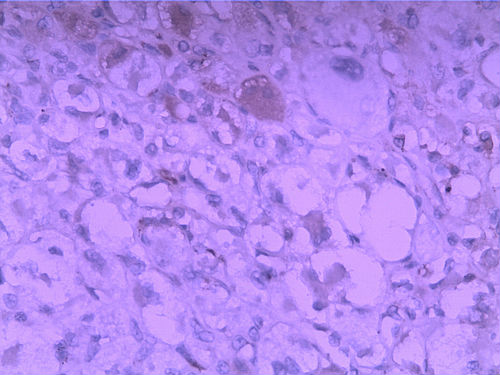

女30Y,大腿肿物5Y,直径3cm

图1

图2

图3

图4

图5

图6

CK,S100,HMB45均阴,Ki67 4%,